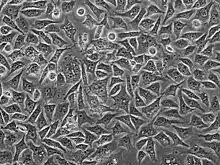

PC3 (PC-3) is a human prostate cancer cell line used in prostate cancer research and drug development. PC3 cells are useful in investigating biochemical changes in advanced prostate cancer cells and in assessing their response to chemotherapeutic agents. PC3 cells are also used to study viral infection in mammalian cells that exhibit an immune response[1]

The PC3 cell line was established in 1979 from bone metastasis of grade IV of prostate cancer in a 62-year-old Caucasian male.[2] These cells do not respond to androgens, glucocorticoids or fibroblast growth factors,[3] but results suggest that the cells are influenced by epidermal growth factors.[4] PC3 cells can be used to create subcutaneous tumor xenografts in mice to investigate the tumor environment and therapeutic drug functionality.

PC3 cells have high metastatic potential compared to DU145 cells, which have a moderate metastatic potential, and to LNCaP cells, which have low metastatic potential.[5] Comparisons of the protein expression of PC3, LNCaP, and other cells have shown that PC3 is characteristic of small cell neoendocrine carcinoma.[3]

PC3 cells have low testosterone-5-alpha reductase and acidic phosphatase activity, and do not express PSA (prostate-specific antigen). Furthermore, karyotypic analysis has shown that PC3 are near-triploid, having 62 chromosomes. Q-band analysis showed no Y chromosome. From a morphological point of view, electron microscopy revealed that PC3 cells show characteristics of a poorly-differentiated adenocarcinoma. They have features common to neoplastic cells of epithelial origins, such as numerous microvilli, junctional complexes, abnormal nuclei and nucleoli, abnormal mitochondria, annulate lamellae, and lipoidal bodies.